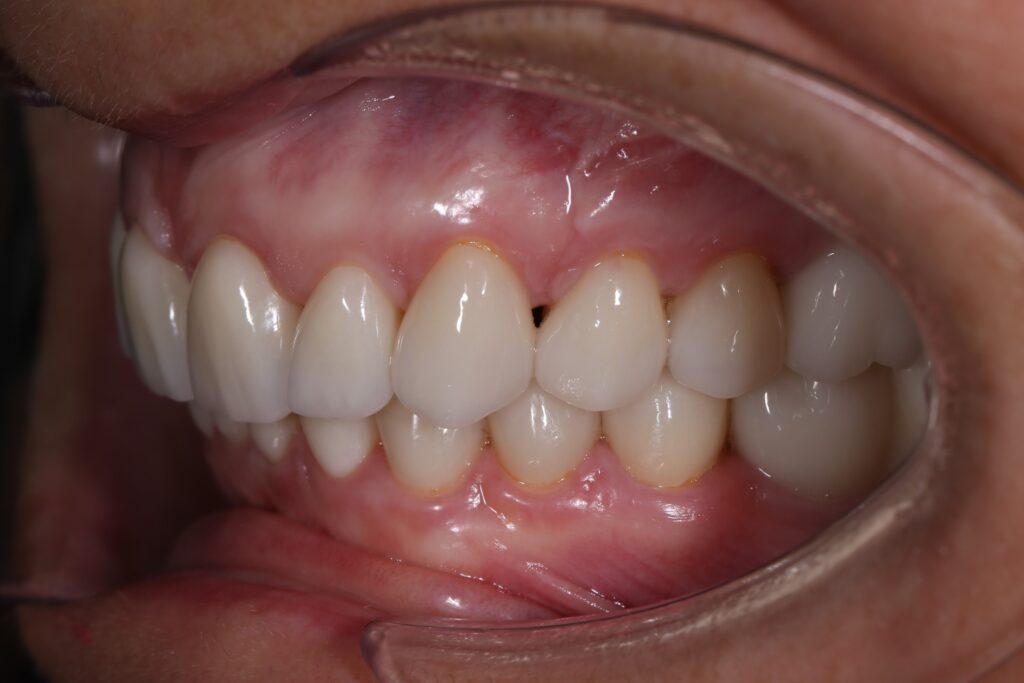

Этап имплантации и протезирования и результаты

Затем были установлены имплантаты Megagen AnyOne.

Спустя 3 месяца после установки имплантатов была произведена замена несостоятельных реставраций и пломб для избежания развития вторичного кариеса под винирами и коронками.

Сделано препарирование зубов на верхней и нижней челюстях с контролем глубины (0.7-0.8 мм) под керамические реставрации. Сняты оттиски с имплантатов.

Установлены временные виниры и коронки из пластика. Спустя 26 дней были зафиксированы керамические виниры и коронки на своих зубах и циркониевые коронки на имплантатах.